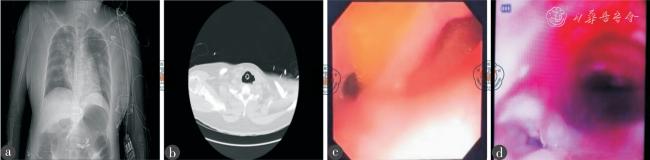

病例1,女,33 岁,精神分裂症患者,因水中毒后意识障碍、抽搐予外院气管插管,拔管后转病房出现反复发热、咳嗽咳痰、氧合下降,为进一步治疗转至我院。入我科时患者呼吸衰竭、躁动、呛咳明显,予气管插管,插管后气囊漏气明显,排除医源性原因后漏气无改善,为明确原因行CT 检查,立位胸部平片及肺部CT 平扫提示气管近端异常扩张、胃及腹盆腔肠道广泛扩张积气(图2a ~b),气管食管瘘待排。立即行床边胃镜及气管镜检查,明确为气管食管瘘(图2c ~d)。耳鼻喉科医生予手术室行气管食管瘘修补+气管切开术,患者术后颈部可见约6 cm×5 cm 手术疤痕,后继发切口感染。每日频繁消毒更换气切纱布及银离子敷料,气切口渗液及周围红肿且有大量黄脓分泌物,声门下吸引管频繁堵塞,引流不畅,支气管吸取物及气切口分泌物均培养出肺炎克雷伯菌、肺炎链球菌,常规气囊压力情况下,漏气明显,结合气道三维重建不排除气切套管尺寸不足可能。8月6日予更换8#Covidien 加强型气切套管,漏气问题明显改善,但无声门下引流装置,气切口分泌物无法引流,保守治疗16 d 切口感染无明显改善,予安装改良的简易负压吸引装置,更换5 次持续吸引8 d 后切口敷料干燥无渗液,分泌物培养阴性,切口愈合良好。

图2 一例典型困难气管切开患者的影像图

注:a 图为胸腹部平片,提示气管近端异常扩张,胃及腹盆腔肠道广泛扩张积气;b 图为CT 横切面,提示疑似气管食管瘘;c 图为胃镜检查,证实气管食管瘘;d 图为气管镜检查,证实气管食管瘘